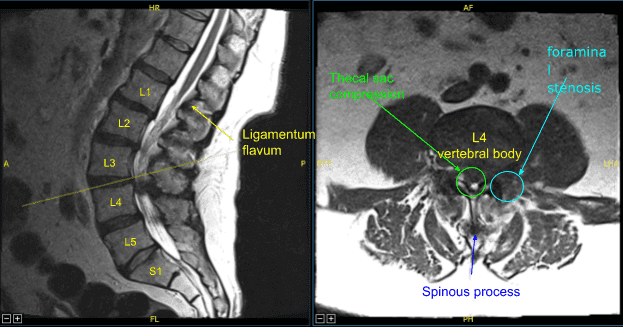

El ligamento flavo estaba expuesto y se observó que estaba significativamente hipertrofiado. Se observaron cambios artríticos extensos y osteofitos en esta parte de la columna. Se usaron rongeurs de Kerrison para resecar el ligamento flavum, dejando al descubierto la duramadre.

La descompresión se continuó lateralmente hasta que el saco tecal se descomprimió completamente. Mientras descomprimía el hueco lateral con rongeurs de Kerrison y exploraba el hueco lateral con instrumentos de Penfield, se observó una cantidad muy pequeña de fluido transparente. No se determinó si esto era secundario a un quiste sinovial observado en la resonancia magnética preoperatoria o a una fuga de líquido cefalorraquídeo.